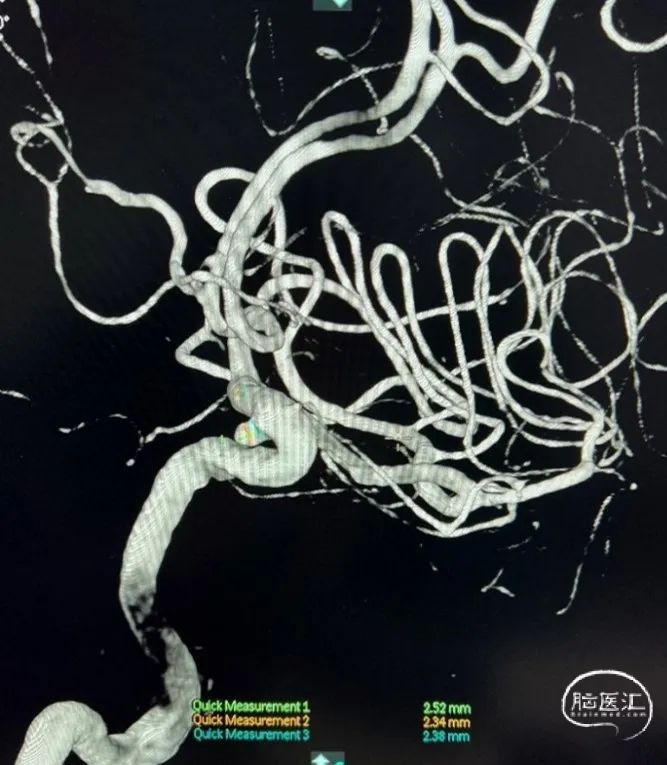

DSA:L-C5 AN,大小约2.5mm*2.3mm。

术前3D:动脉瘤大小约2.52*2.34mm,颈宽约2.38mm,载瘤动脉近端约3.63mm,远端4.08mm。

支架:Neuroform Atlas 4.5*21mm

预填部分2mm*4cm Target弹簧圈进行成篮,然后将4.5*21mm Atlas支架到位并进行半释放,半释放支架后,继续填入2mm*4cm Target弹簧圈。

将Atlas支架全部释放(如左动态影像)

Target 2mm*4cm弹簧圈成篮满意,支架打开良好。